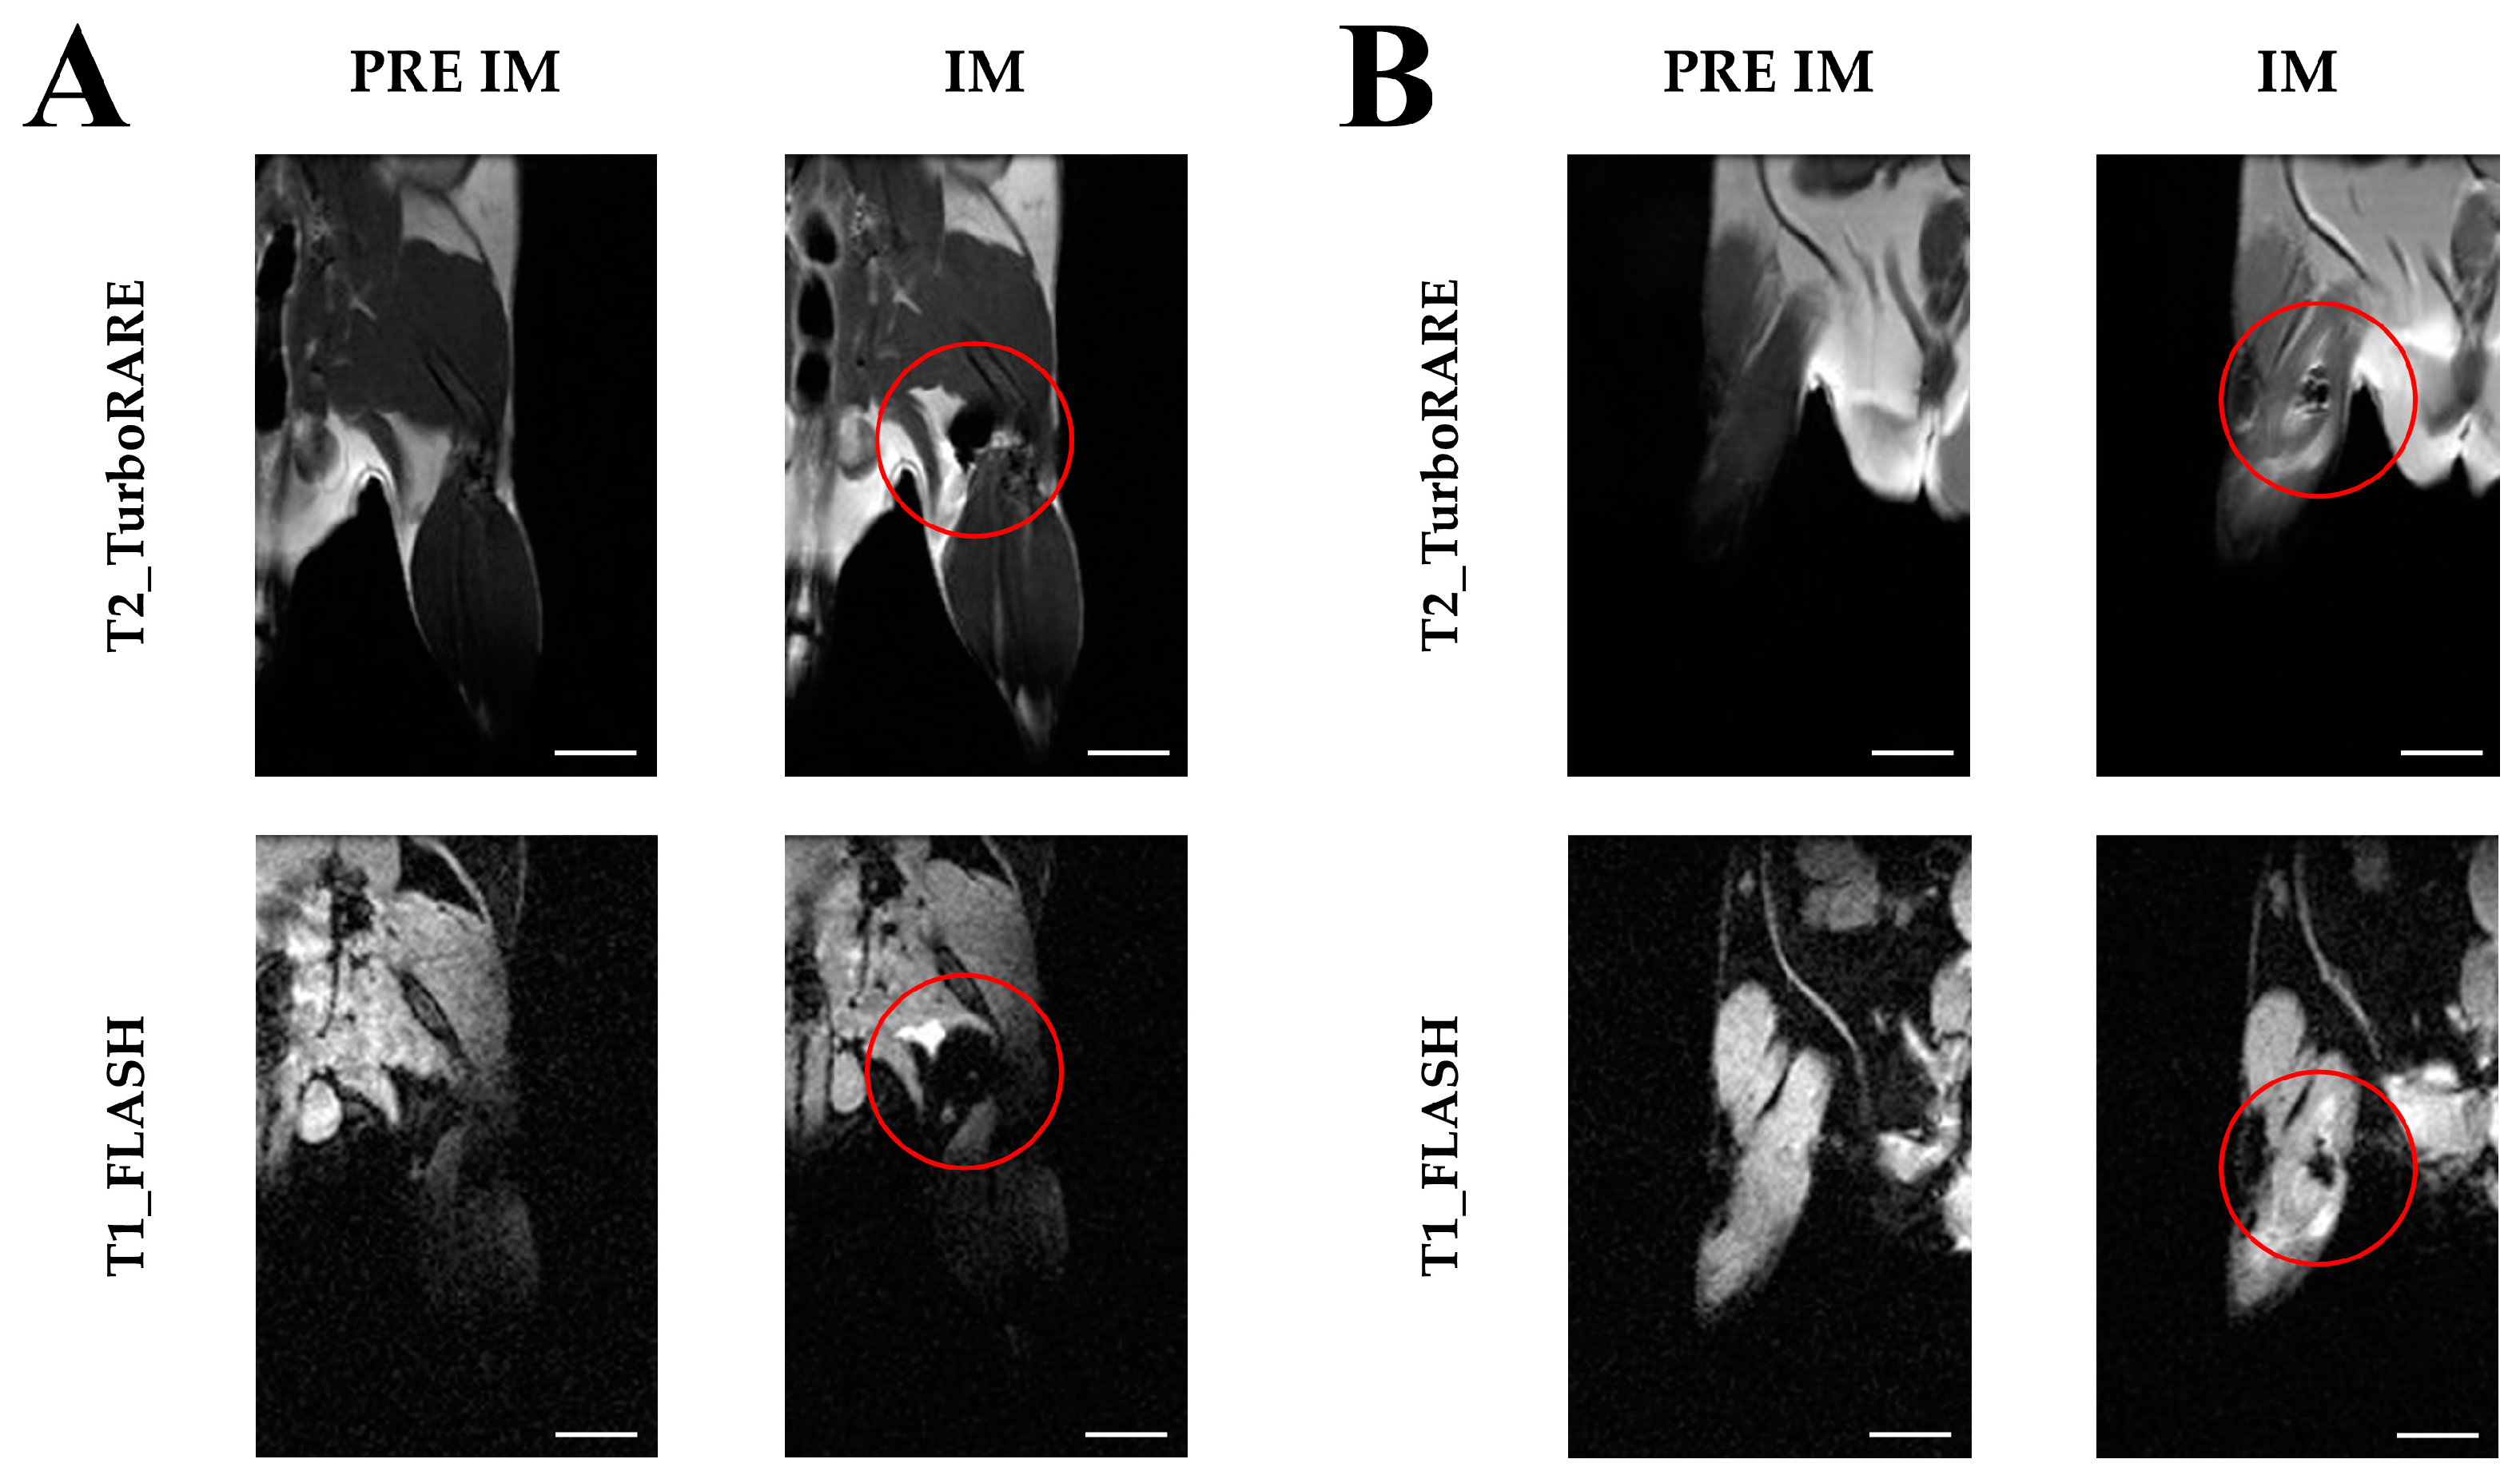

2.4. Extraction of Extracellular Vesicles from ADAS-Labeled Cells

4.4. Extraction of Extracellular Vesicles from ADAS-Labeled Cells